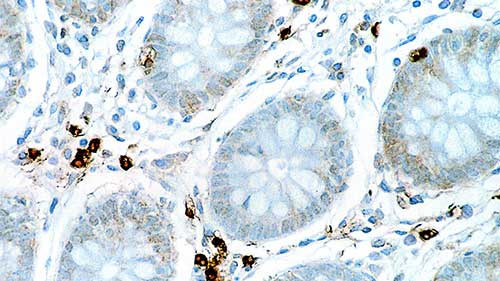

Human colon: immunohistochemical staining for Interleukin 6. Note cytoplasmic staining of a proportion of lymphoid cells. Interleukin 6: clone 10C12

Interleukin 6